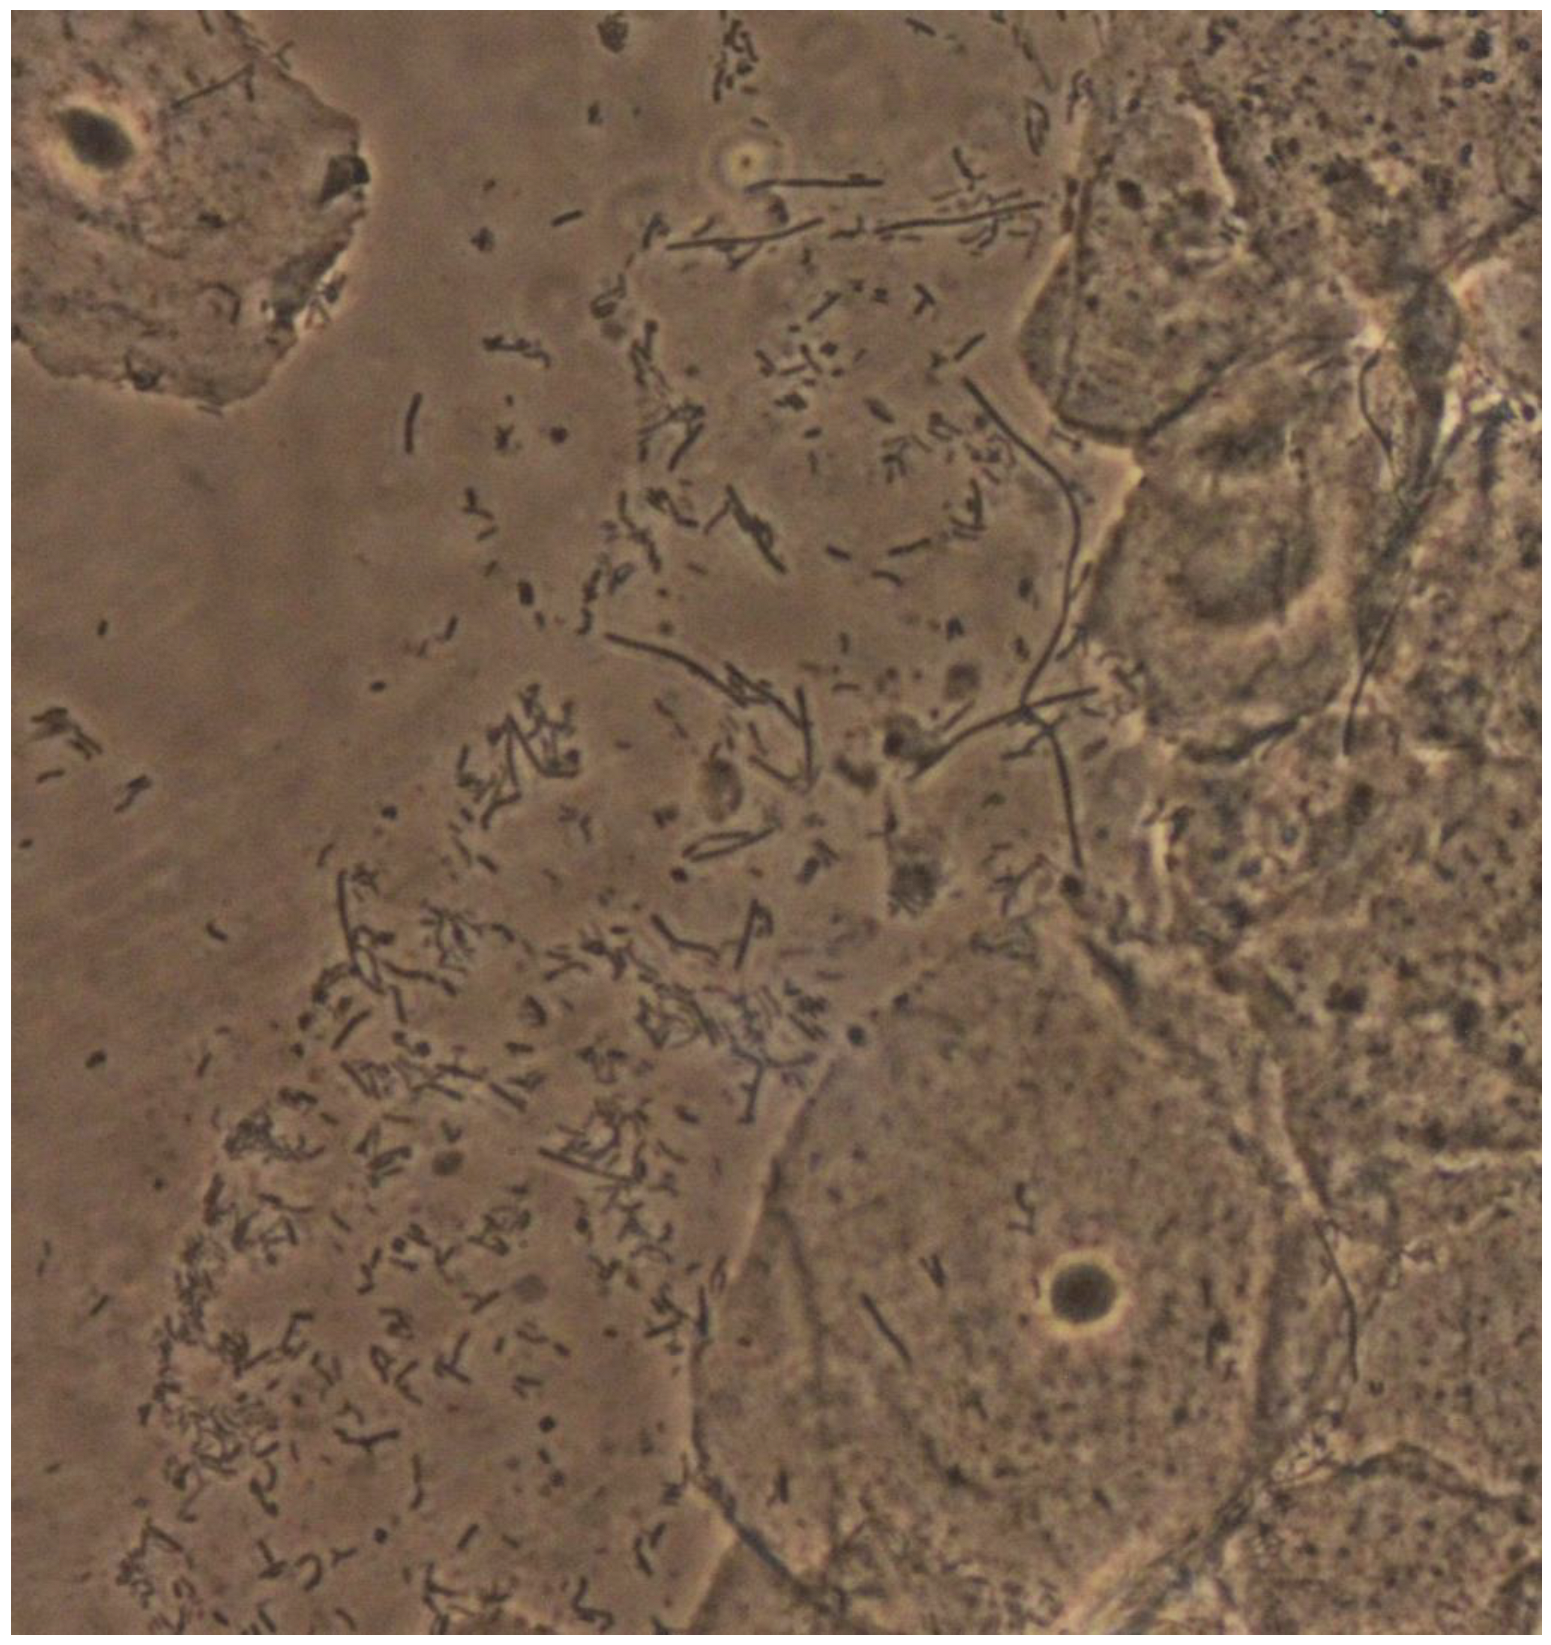

Vaginal Leptothrix: An Innocent Bystander?

- Vieira-Baptista, P.; Grincevičienė, Š.; Oliveira, C.; Fonseca-Moutinho, J.; Cherey, F.; Stockdale, C.K. The International Society for the Study of Vulvovaginal Disease Vaginal Wet Mount Microscopy Guidelines: How to Perform, Applications, and Interpretation. J. Low. Genit. Tract Dis. 2021, 25, 172–180. [Google Scholar] [CrossRef]